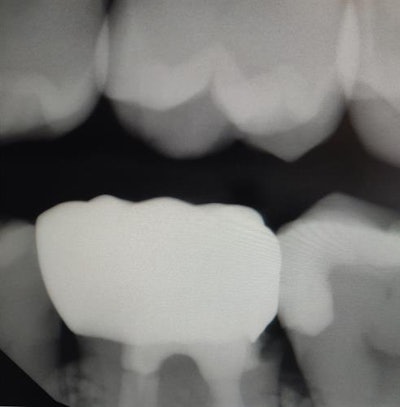

Cummings said there was deep decay lending to deep subgingival margins of the preparation, and multiple unsuccessful attempts were made by the lab to close the margin (the "before" image below, along with an "after" image showing the result of in-office milling).

"The details that the lab could not capture the first three times, we successfully duplicated and milled on the first try with our new in-office technology solution," she said. "I was able to draw the margin exactly where I wanted it and provide a superior restoration on the first effort.